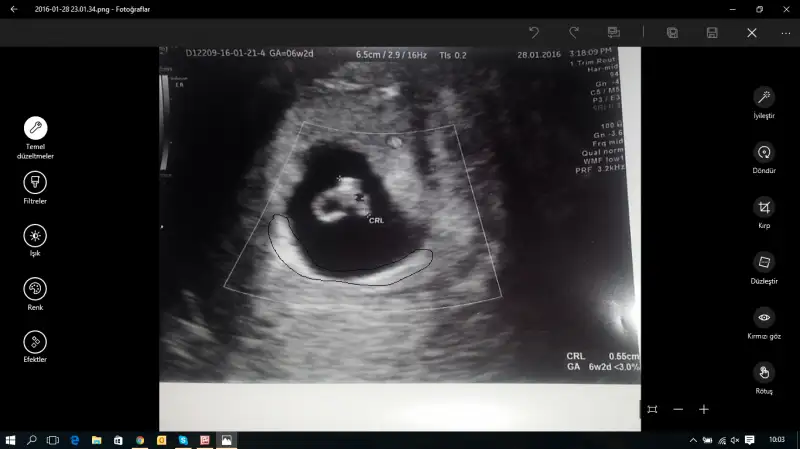

Vajinal ultrasonla bakildi 6+2 bir tahmininiz var mi? Crl diye olculen yer bebekmiş

tüm yorumları okudum, normalde anladığım yok ama arkadaşların yaptığı yorumlara göre senin plasenta solda görünüyor sanki ve vajinal olunca kız bebek demiş arkadaşlar ama bilemiyorum tabiii...